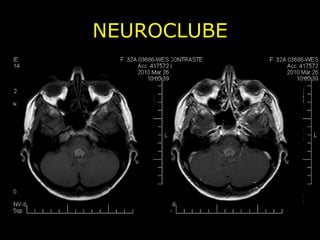

NEUROCLUBE